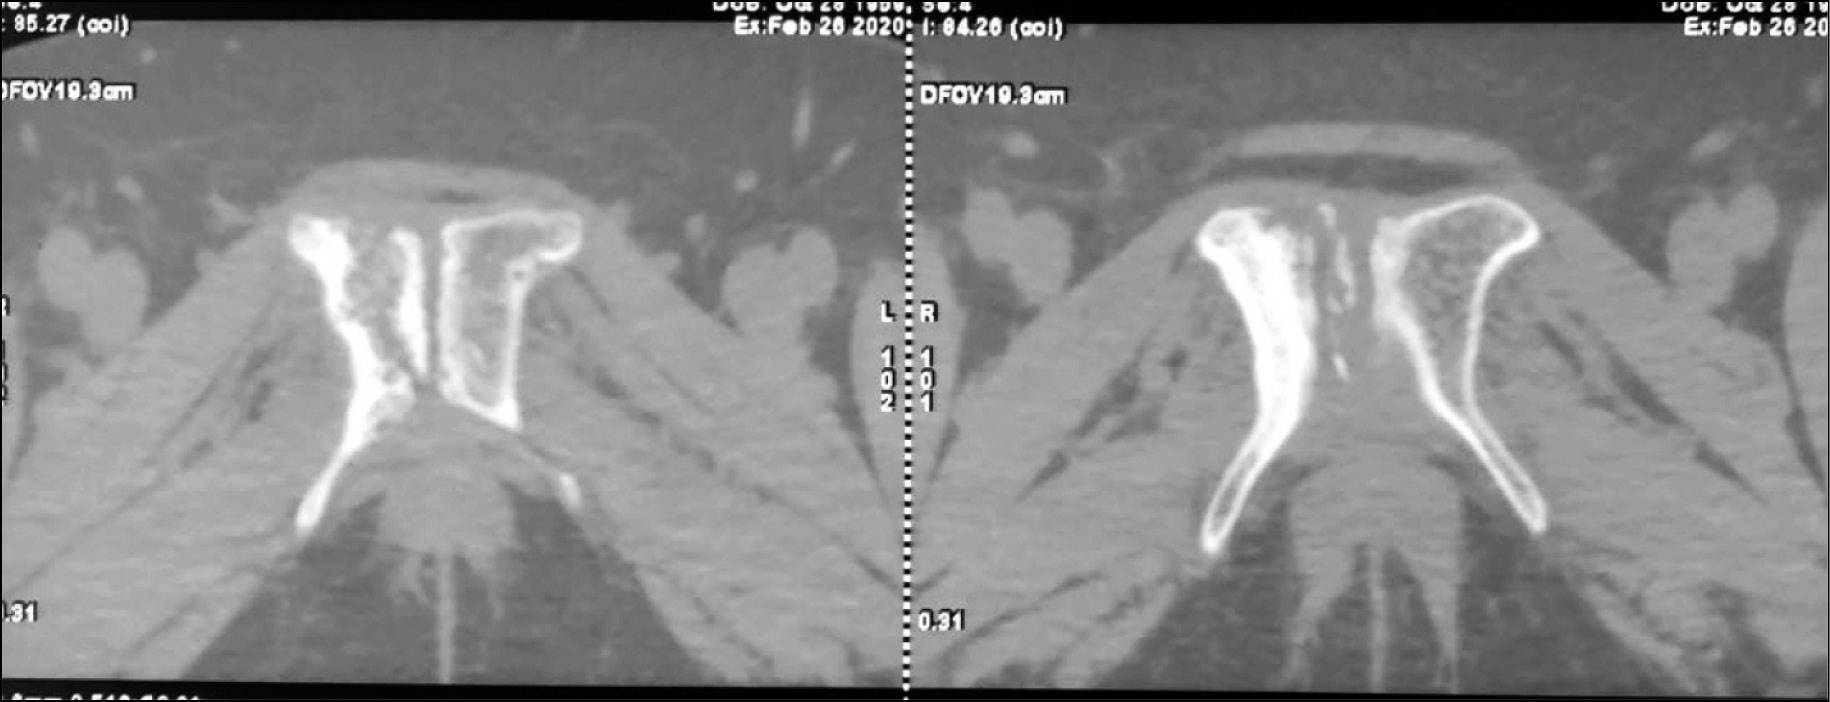

На компьютерной томограмме (КТ) костей таза от 26.02.2020: перелом ветвей правой лонной кости на уровне лонного сочленения, признаки консолидации не выражены (рис. 1, 2).

Рис. 2. Компьютерная томограмма костей таза пациентки Д.: признаки консолидации отсутствуют.

Fig. 2. CT scan of the pelvic bones shows no signs of consolidation.